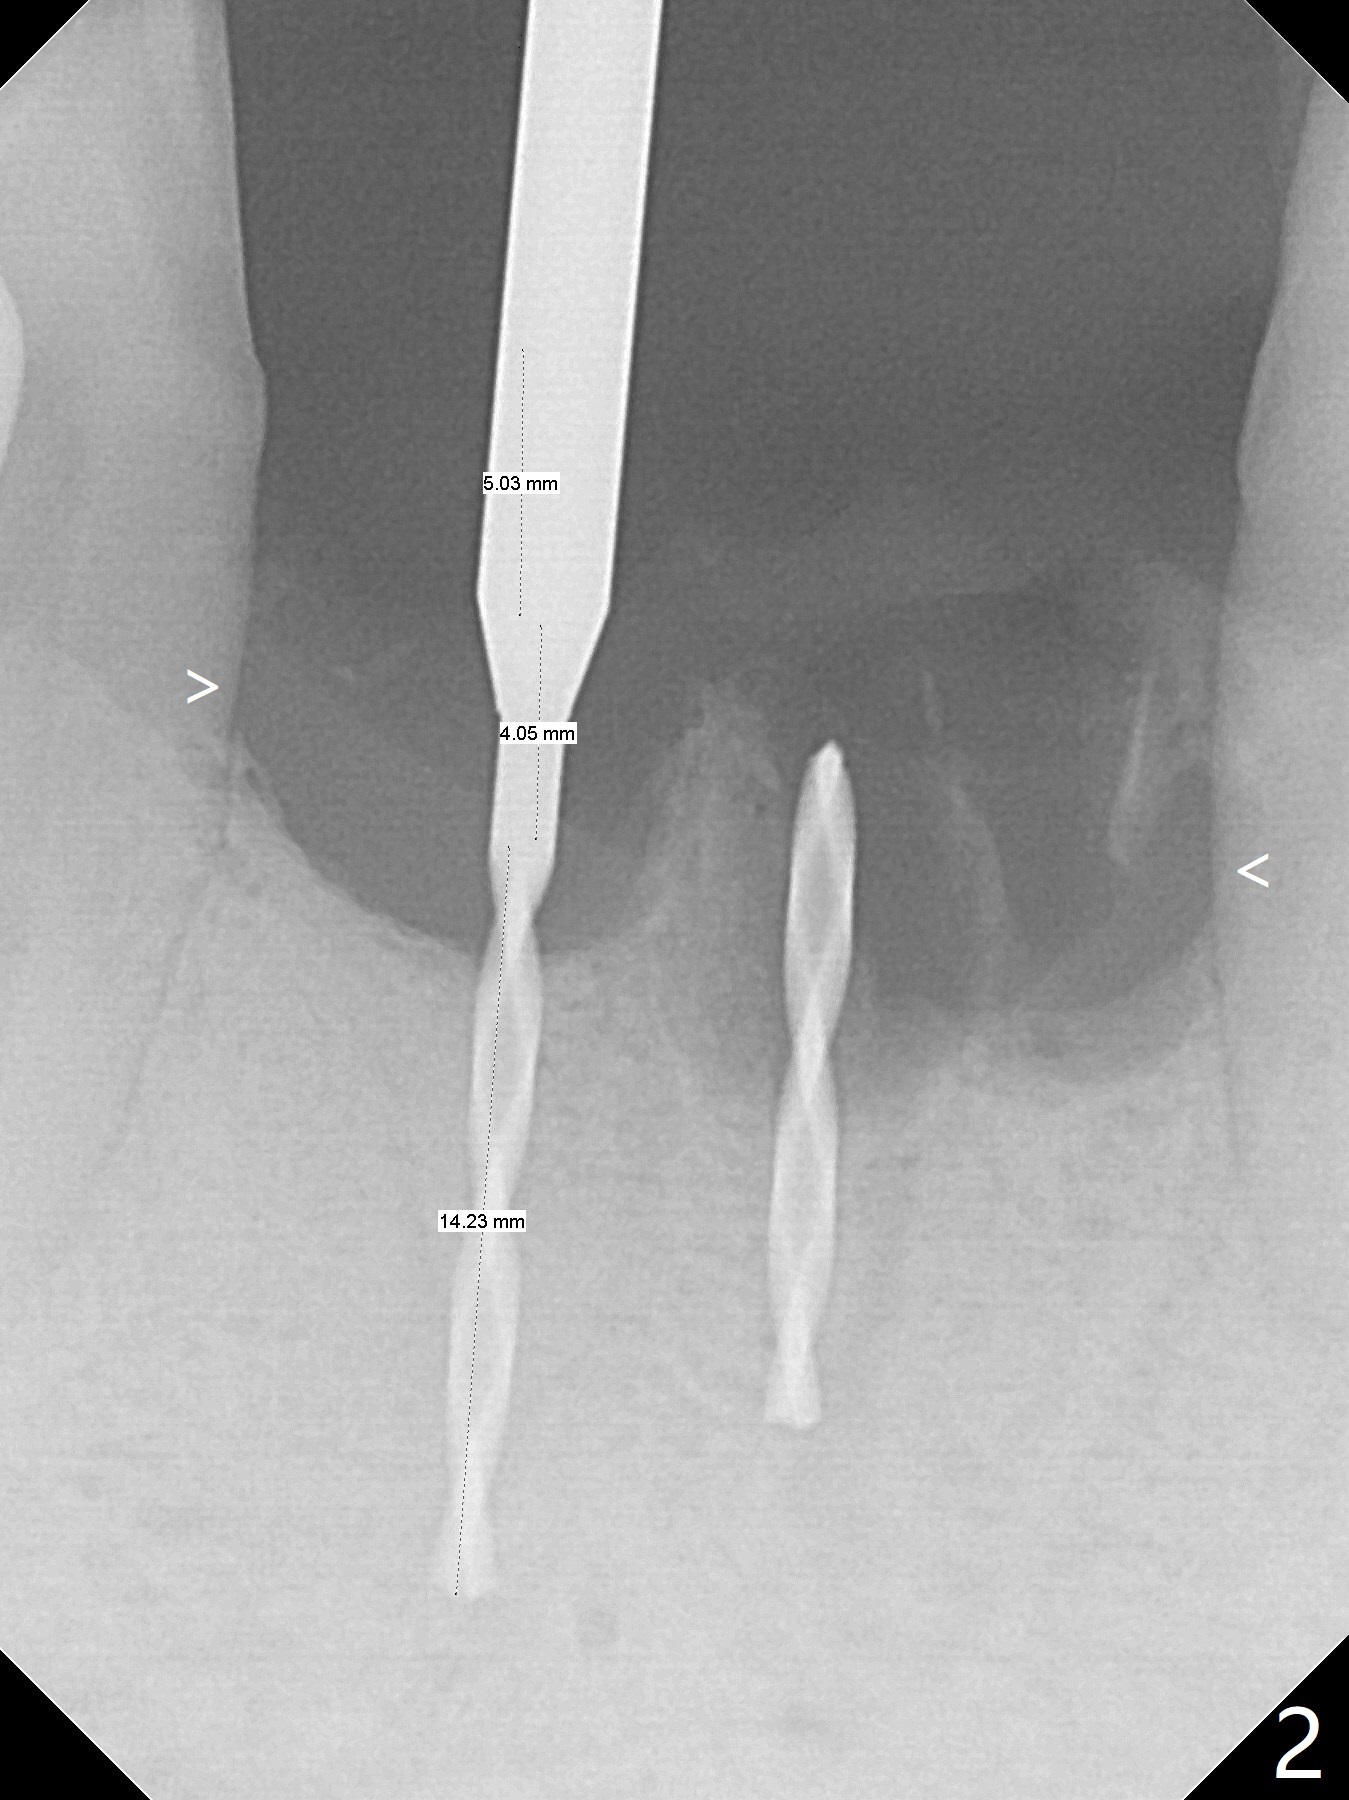

When the patient (smoker) returns for treatment, the apical abscess associated with #25 and 26 reduces with oral Amoxicillin. He agrees with 4 incisor extraction because of 2 apical fistulae (Fig.1 >). Osteotomy starts at the central incisor sockets due to mesial root exposure of the canines (Fig.2 arrowheads) and buccal alveolar bone fracture between #23 and 24 (Fig.7). Two of 3x14(4) mm 1-piece implants are placed with ~ 2 mm buccal gap (Fig.3). After Vanilla graft is placed in the bony defects (Fig.5 *) and Osteogen plug, sutures are placed (Fig.4). The implants are then placed deep to decrease thread exposure (Fig.6). Periodontal dressing is applied instead of provisional. Alveolar bone fracture between #23 and #24 accounts for why an implant is less suitably placed at #24 (Fig.7). Three months postop, composite is added to the pontic areas of the provisional (Fig.8 *). When the provisional is seated, the convex pontics press the used-to-be-flat gingiva (Fig.9 arrows). Thus the concave gingiva forms (Fig.10 *) with corresponding papillae (^). In fact the photos of Fig.8-10 is taken ~3 weeks later. Most of the grafted bone remains in place 3.5 months postop (Fig.11). A piece of floss with 2 knots in one end is placed between the middle units of the final bridge before cementation (Fig.12 (4 months 10 days postop)). In fact removal of residual cement is not so simple. It is tedious (Fig.13,14). An asymptomatic buccal fenetration with implant thread exposure is found 2 months post cementation and persists for another month in spite of advice to reduce smoking (1/2 ppd) and use of water pik (Fig.15). The area will be debrided, followed by bone graft and PRF in a month.